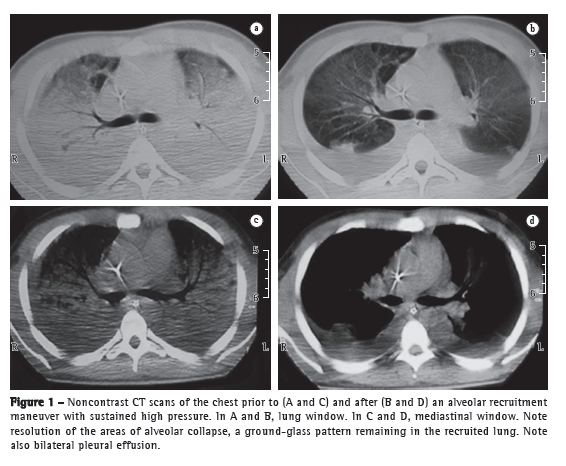

Because the patient presented with refractory hypoxemia, a CT scan was taken. During the procedure, an ARM was performed. The patient remained properly sedated and was hemodynamically stable. He was submitted to pressure-controlled ventilation (PCV), as follows: RR, 15 breaths/min; inspiratory time, 2 s; inhalation/exhalation ratio, 1:1; FiO2, 1; and pressure, 15 cmH2O above a positive end-expiratory pressure (PEEP) of 25 cmH2O for 2 min. The functional and radiological responses were evaluated immediately before the ARM (PaO2/FiO2 ratio = 65; PaO2 = 58.9 mmHg; and FiO2 = 0.9) and approximately 20 min after the ARM (PaO2/FiO2 ratio = 102; PaO2 = 71.9 mmHg; and FiO2 = 0.9). The CT scans revealed aeration of the areas of alveolar collapse, with persistent ground-glass areas in the recruited lung (Figure 1). After having performed the ARM, we calculated the ideal PEEP with the patient still on PCV. The PEEP that resulted in the highest tidal volume and therefore the best static compliance was determined on the basis of a PEEP of 25 cmH2O reduced by 2 cmH2O every 2 min and was found to be 15 cmH2O, to which 2 cmH2O were subsequently added. In order to guarantee the stability of tidal volume and alveolar pressure, we chose to switch from PCV to volume-controlled ventilation, in accordance with the protective ventilatory strategy (tidal volume = 6 mL/kg of ideal weight). Plateau pressure was monitored and maintained at less than 30 cmH2O.